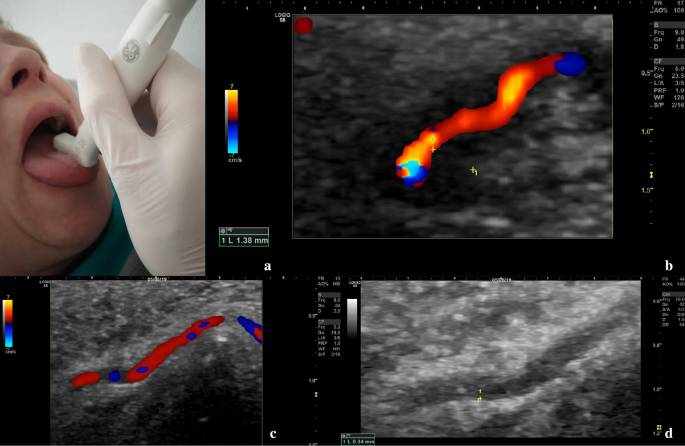

Furthermore, due to tongue claudication and lingual pain, the deep lingual artery, which is a branch of the lingual artery, branching from the external carotid artery, was also examined by ultrasound. It displayed a typical vasculitic halo-sign (Fig. 3). Vasculitic IMT swelling led to markedly reduced blood flow and visible IMT thickening in B-mode. Peak IMT of the lingual artery was 1.38 mm. There was no occlusion of the lingual artery. This sonographic finding explained the patient´s symptoms of thrusting pain of her tongue.

Ultrasound examination of the lingual artery with an 18 MHz hockey stick probe. a Position of the ultrasound probe on the patient´s tongue. b Doppler ultrasound and intima-media thickness (IMT) values of the affected deep lingual artery. c Doppler ultrasound of the deep lingual artery on 6-month follow-up, reduced field of view. d IMT values of the deep lingual artery on 6-month follow-up in B-Mode, reduced field of view

Three months after dismissal a follow-up examination was performed. The patient was on 9 mg prednisolone per day, 162 mg tocilizumab subcutaneously per week and free of symptoms. CRP was normal. On ultrasound examination a relevant decrease of IMT values could be observed in all affected arteries. IMT of the deep lingual artery had decreased from 1.38 to 0.77 mm. Systolic flow velocities of both central retinal arteries had increased from 8.2 to 21.6 cm/s on the left eye and from 7.5 to 19.1 cm/s on the right eye.

On ultrasound examination, a further decrease in IMT values could be observed (Table 1). Flow velocity of both central retinal arteries showed stable values with 19.1 cm/s on the left eye and 17.2 cm/s on the right eye. IMT of the deep lingual artery had decreased from 0.77 to 0.34 mm.

This case illustrates a rare complication of GCA—vasculitis of the lingual artery, which could be diagnosed and followed-up by modern ultrasound. Clinical presentation of vasculitic affection of the tongue without respective imaging is described only in a few cases in literature [10, 11]. Tongue necrosis is described as a rare but severe complication [2, 12].

This is the first case described in the literature, in which vasculitis of the lingual artery could be assessed and documented by ultrasound.

The role of ultrasound in diagnosis of GCA is known [8]. Apparently, there also seems to be a role in monitoring disease during follow-up examinations. The patient´s follow-up examinations showed a relevant decrease of IMT values over a 6 months period. Nearly all IMT values of examined arteries decreased below the respective cut-off values (Table 1) [7]. IMT values of the lingual artery noticeably decreased from 1.38 mm at diagnosis to 0.34 mm at 6-months follow-up. Further research regarding the role of ultrasound in follow-up is required. In summary, ultrasound can be a helpful and quickly available imaging modality for diagnosis and follow-up of GCA. Nevertheless, an experienced examiner is required to achieve reliable results [4]. Monti et al. recently published an article assessing the role of ultrasound in GCA by reviewing the available literature including recommendations to improve diagnosis of GCA [16].